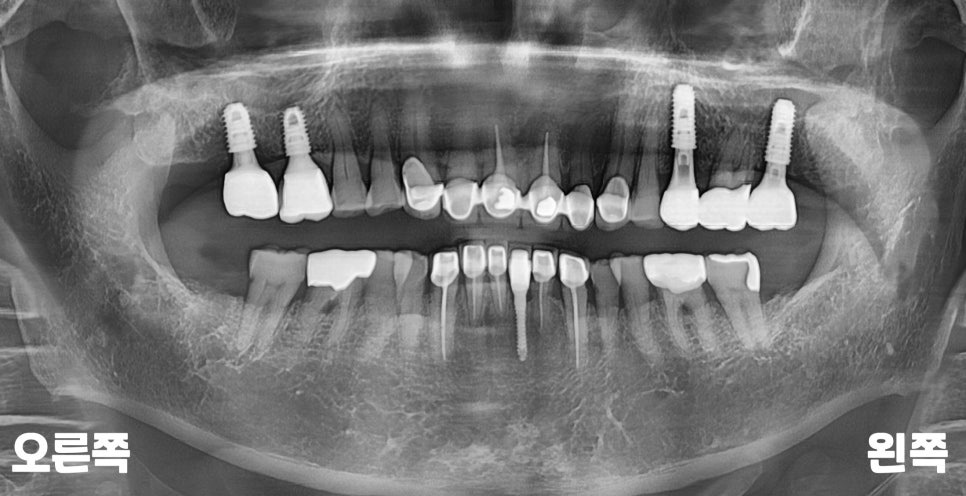

또한 파노라마로

전체적인 입 속 체크를

해 보았을 때,

왼쪽 맨 끝으로 아직

뼈가 덜 아문 흔적이 있습니다.

실제로 여쭈어보니

많이 흔들려서 뽑은지

몇 개월이 지났다고 하셨는데요.

발치 후 기간이나

회복 상태를 봤을 때

서울바르디치과에서

임플란트를 심기에

적절한 모습이었습니다.^^

모든 임플란트 마무리 후에

확인을 위한 파노라마를

추가로 촬영해 보았습니다.

위아래로 교합 라인도

턱지지 않고 잘 맞고,

씹을 때도 높지 않고

편안하다고 해주셨는데요.

앞으로 정기적인

6개월~1년 검진을 통해

불편한 점이 있는지

계속 관리해 드릴

예정입니다.